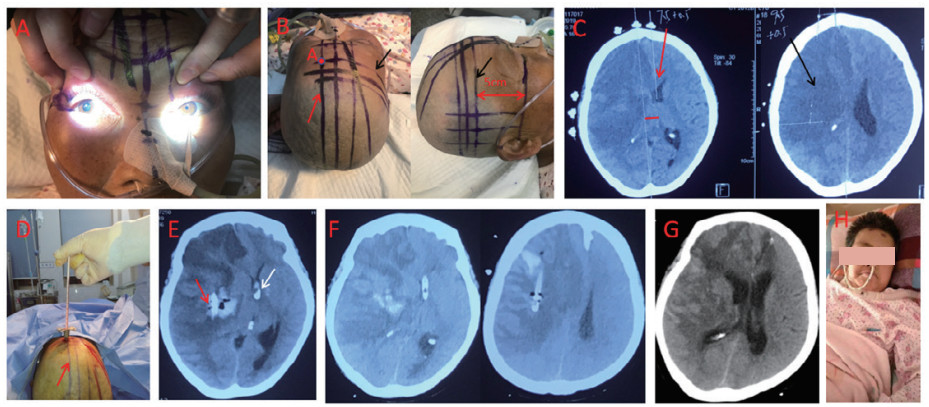

案例1:MMI患者,男,79岁,因“右侧肢体无力4.5 h”入院,经积极内科保守治疗,患者于发病后第4天发生脑疝,第5天死亡(图 1)。

A:A1示发病5 h CTP经rapid软件分析示核心梗死区259 mL(CBF<30%),A2示低灌注区337 mL(Tmax>6 s)。B:CTA示左侧颈内动脉起始端闭塞,闭塞远端血管及侧枝血管未显影。C:发病29hCT示梗死灶>2/3MCA供血区域,中线结构轻度移位。D:发病第3天DWI示继发恶性脑水肿形成,中线移位12 mm,患者持续昏迷,达去骨瓣减压(DHC)指征,患者拒绝DHC。入院第4天脑疝形成,第5天患者死亡 图 1 一例保守治疗老年恶性大脑中动脉梗死患者 Fig 1 An elderly patient with MMI treated with medical therapy alone

案例3:定向置管抽吸联合侧脑室置管外引流治疗老年MMI伴脑疝患者,女,63岁,因“意识模糊伴左侧偏瘫16 h”入院,经治疗6个月后患者能独立行走,mRS评分3分(图 3)。

A:右侧瞳孔散大, 提示右侧钩回疝形成。B:示术前定位和画线,A点侧脑室颅表穿刺点,为OM上5 cm的穿刺横断面线(黑箭头所指)与正中矢状面线右侧旁开1.5 cm的旁矢状面线(红色箭头所指)相交点。C:术前复查CT示中线移位1.5 cm,同侧侧脑室基本压闭。D:术中给予侧脑室置管,方向基本在旁矢状面(红色箭头所指)上。E:术后第1 d复查CT示侧脑室置管位置良好(白色箭头),并可见梗死组织的抽吸导管管头(红色箭头),管头位置少量出血 < 抽吸量的15%。F:病程中根据颅内压和占位效应性梗死组织抽吸20-50 mL/d,术后5 d CT示占位效应未加重。(G:示术后2 w CT示脑室复张,中线移位恢复基本正常。H:术后2月随访神志清楚,mRS=4分 图 3 定向抽吸坏死脑组织联合侧脑室置管外引流治疗老年MMI伴脑疝形成 Fig 3 Stereotactic aspiration of necrotic brain tissue combined with lateral ventricular catheter drainage for an elderly patient with MMI accompanied by cerebral herniation